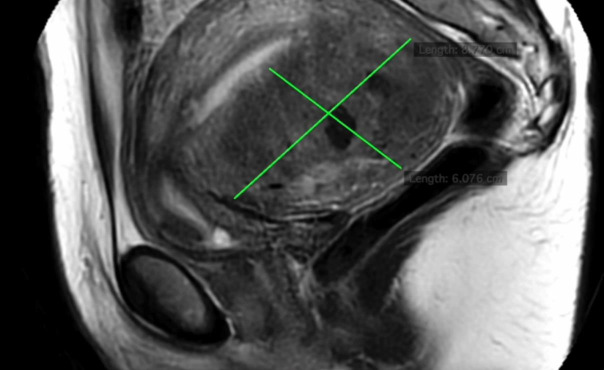

Objectives: To provide a step-by-step video demonstration of robotic-assisted excision of diffuse adenomyosis affecting the posterior uterine wall.

Materials and methods: This video article describes the use of a robotic platform in conjunction with intracavitary indocyanine green (ICG) for the uterus-sparing excision of diffuse adenomyosis.

Results: A 38-year-old nulligravid patient with a history of chronic pelvic pain and infertility underwent surgical management of adenomyosis following two unsuccessful IVF cycles. The excisional surgery resulted in minimal blood loss (60 ml) and the patient was discharged on the same day of surgery with no complications.